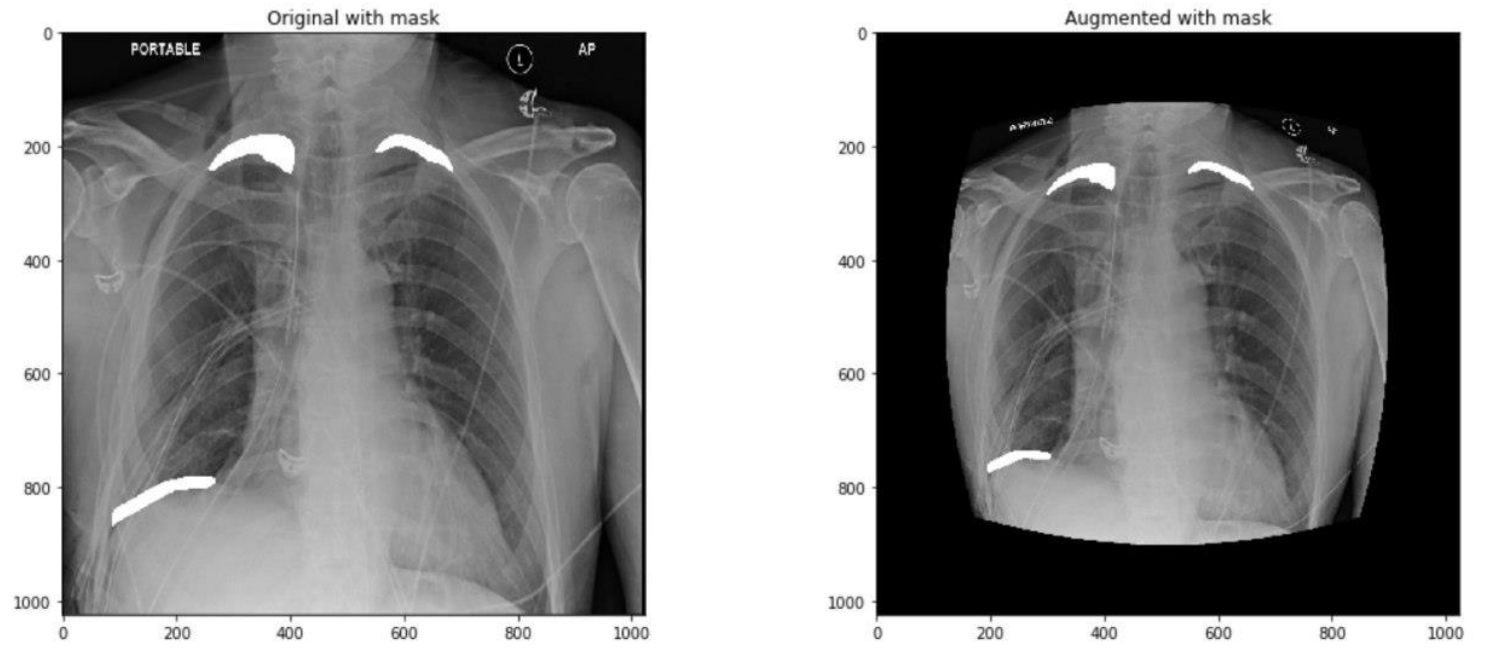

3.1 Data Augmentation

这里模型的输入是1024X1024X3的胸片和1024X1024X1的mask。作者直接使用了图像增强库 albumentations 对数据进行增强,作者使用了一个较为复杂的方案:以固定顺序对图像进行不同的变换,并且给予每种方法一定的概率,使增强方法的运用随机化。具体如下:

- HorizontalFlip:0.5

- OneOf:0.3

- RandomContrast:0.5

- RandomGamma:0.5

- RandomBrightness:0.5

- OneOf:0.3

- ElasticTransform:0.5

- GridDistortion:0.5

- OpticalDistortion:0.5

- ShiftScaleRotate:0.5

上面小数表示此增强方法运用的概率,OneOf表示在其子方法中选择一个。

需要注意的是,这里有2个OneOf,第一个OneOf下面的增强方法主要对图像的亮度、对比度等进行调整,而第二个OneOf下面的增强方法主要对图像的形状进行调整。可以看几个例子。

因为训练模型分成四个阶段,每个阶段使用的数据是一样的,使用一定概率给图像做增强,实际上保证了每个阶段实际参加训练的数据都不完全一样。